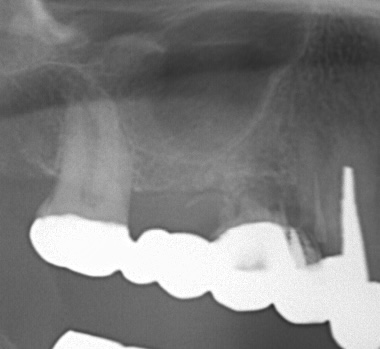

| 治療名 | サイナスリフトを併用したインプラントブリッジ症例 |

| 治療説明 |

奥歯に入っていたブリッジの支台歯にむし歯が見つかり、やむを得ず抜歯となりました。結果として奥歯が3本分欠損したため、患者さんとの相談のうえ、インプラントによる治療を選択しました。 |

| 治療回数・期間 | 約9ヶ月 |

| 副作用とリスク | ・入れ歯や従来のブリッジと比べ、治療期間が長くなる場合があります。 ・骨造成(GBRやサイナスリフト)を伴う場合、さらに治療期間が延びることがあります。 ・インプラント手術後には、一時的に違和感、痛み、腫れ、出血が生じることがありますが、通常は2日〜1週間で落ち着きます。 ・サイナスリフトは、まれに上顎洞への感染リスクがあるため、術後の経過観察が重要です。 |

| 料金(税込) | 小規模GBR:110,000円 サイナスリフト:220,000円 インプラント一次手術×2本:440,000円 二次手術×2本:110,000円 上部構造〈インプラントブリッジ〉:495,000円 合計:1,375,000円 |